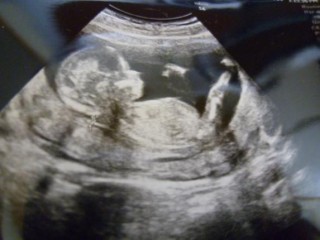

今日は起きていてくれたので、いろんな仕草が観えました。 先生が上手に撮ってくださり、何気に鼻の高い子に見えるのはすでに親バカでしょうか?

双角子宮ですが、今のところ張りも出血もありません。 このまま何事も無く育って欲しいものです。

背骨まではっきり写っていて、思わず「うわ~ぉ」と言ってしまいました。主人に写真を見せたら、頭の形が俺に似ている!と…。早くも親バカですね♪(笑)

CRLは79.8㎜でした。